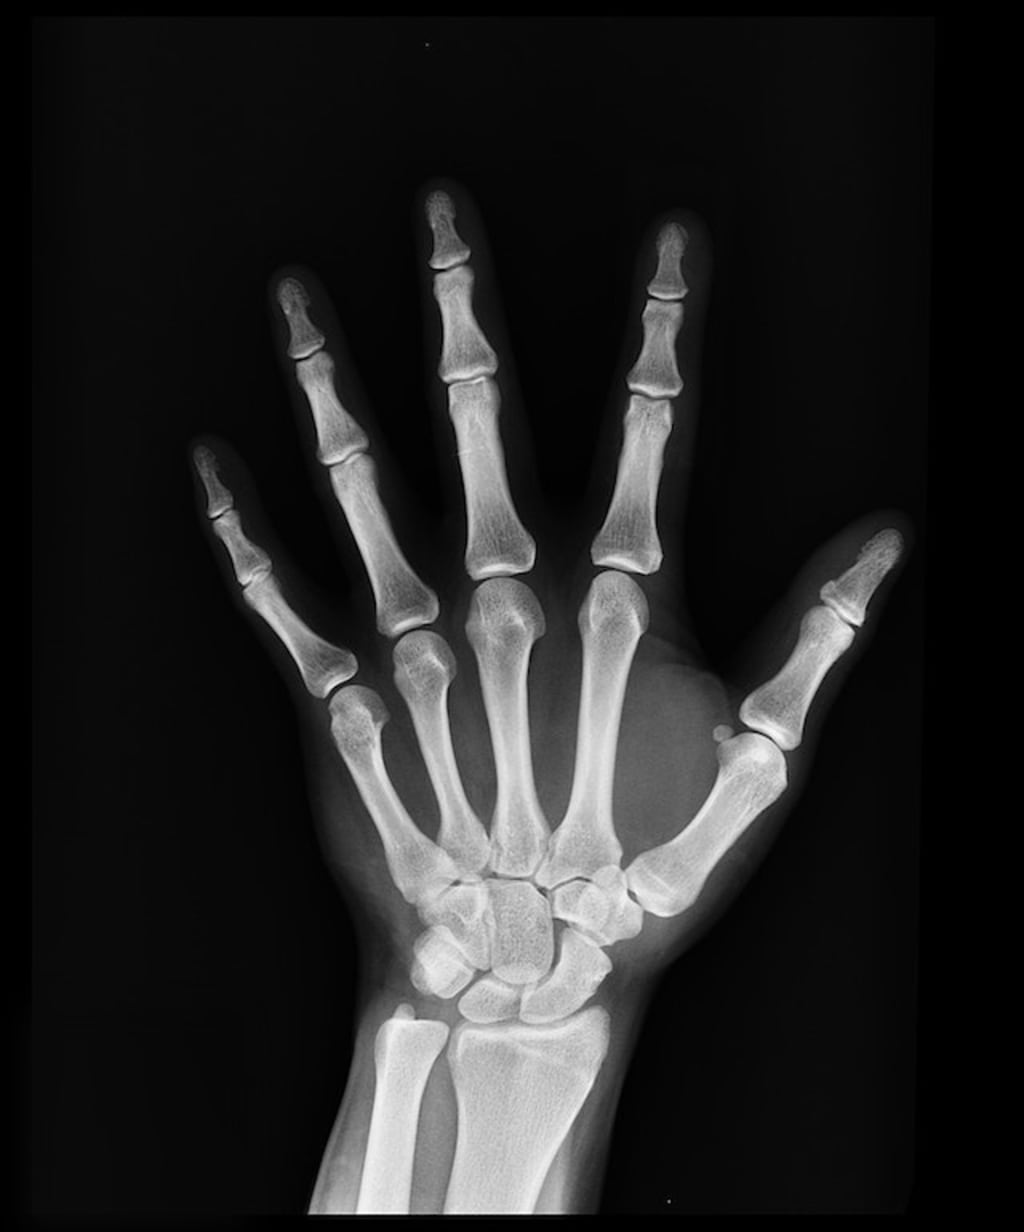

Curious, the duo embarked on a daring quest. By meticulously examining X-rays by chiropractors of people between the ages of 18 and 86, they have managed to unlock the secrets hidden in our bones. What they discovered was dizzying. Young people, enamored in the digital realm, have amazingly lingering EOP rates. The tantalizing hypothesis emerged - hours spent poring over screens created a new reality. When the neck instinctively stretches forward, the delicate balance of our cervical ligaments shakes. The pressure mounts, unleashing a series of spectacular changes. Millimeter by millimeter, the EOP gradually expanded, reaching unprecedented lengths. This was the birth of the "archaic writing", a curious phenomenon that primarily marked the male population.